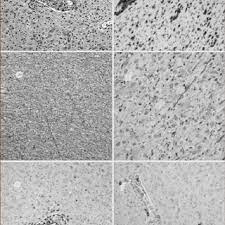

En la esclerosis múltiple, la histología o estudio de los tejidos del sistema nervioso reveló que hay un proceso de inflamación que daña la capa de mielina pueden compararse tratamientos en función de la histología de la esclerosis múltiple, diseñando planes terapéuticos con aquellos que han. Esclerosis multiple la degeneración axonal es un proceso que ocurre como consecuencia de una amplia variedad de trastornos metabólicos, tóxicos, hereditarios e inflamatorios los impulsos nerviosos que pasan por esos sitios se interrumpen y en ocasiones quedan totalmente bloqueados.(5). Antonio robles gentile médico c.c., centros asistenciales getafe y pinto correspondencia: Multiple sclerosis (ms) causes, signs and general information at patient.info. Este material puede ser reproducido total o parcialmente para fines de diseminación y capacitación.